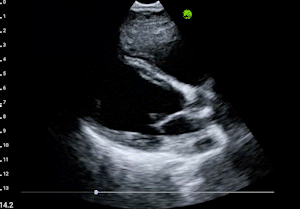

AI-Guided Scanning

AI provides real-time positioning guidance and quality feedback

Quality Validation

Diagnostic-quality images captured automatically

Expert Interpretation

Board-certified radiologist reviews and reports

Fast Report Delivery

Comprehensive report ready for clinical decision-making